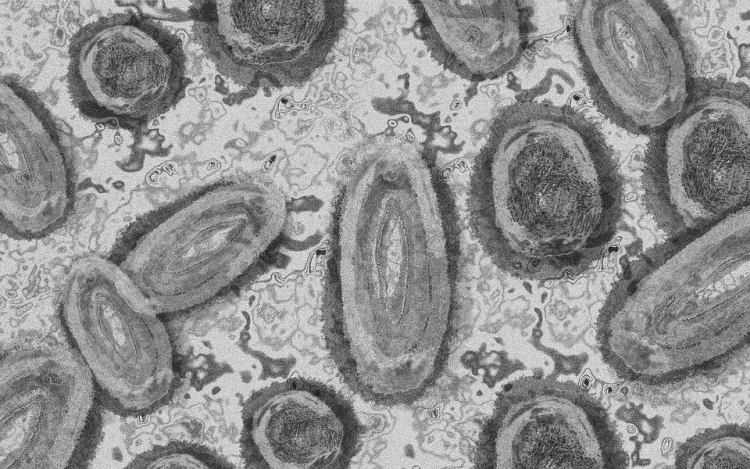

Meghaladta a 13 ezret a majomhimlő-fertőzöttek száma az Egyesült Államokban

Meghaladta a 13 ezret a majomhimlő-fertőzöttek száma az Egyesült Államokban, a legtöbb esetet Kaliforniában és New York államban regisztrálták.

Az amerikai járványügyi és betegségmegelőzési központ (CDC) szerdán közölt friss tanulmánya szerint a járvány ugyan elsősorban szexuális érintkezés útján terjed, de a fertőzöttek egy része tömegrendezvényeken kapta meg a vírust. A hivatal arra hívja fel a figyelmet, hogy a majomhimlővel bárki megfertőződhet, ha másokkal közeli testi kapcsolatba kerül, akár bőrfelületek érintkezése révén.

A legutóbbi adatok szerint 13 500 fölött van az igazolt fertőzöttek száma, az esetek csaknem felét Kalifornia, New York és Florida államokban regisztrálták.